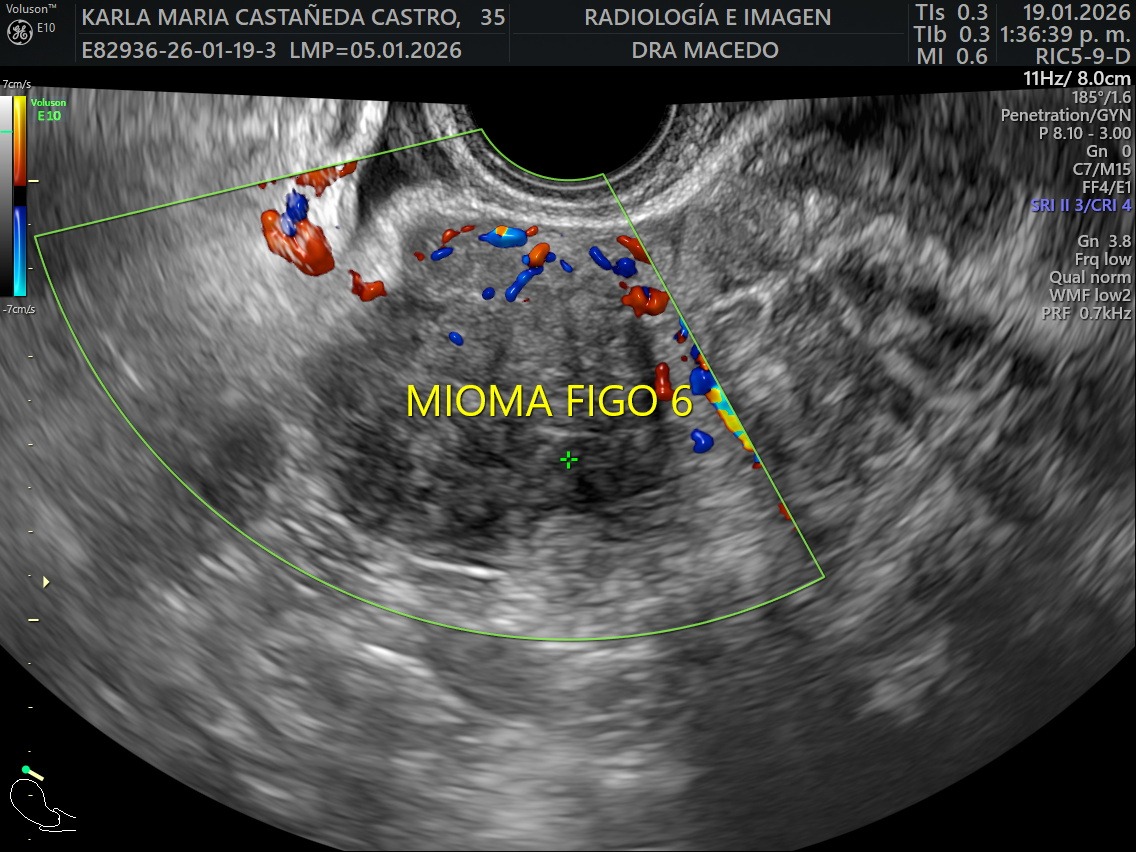

I was recently diagnosed with 16 large uterine fibroid tumors (myomas). My doctors have told me that I need immediate major surgery to remove them. The procedure I will undergo is an Open Abdominal Myomectomy, along with a biopsy to ensure there are no cancerous cells. I will also need to stay in the hospital for approximately five days during recovery. Although even if the tumors are benign, they are putting extreme pressure on my surrounding organs causing significant pain, bleeding, fatigue, and health related issues on a daily basis.

Recientemente me diagnosticaron 16 tumores de fibromas uterinos (miomas). Mis médicos me han informado que necesito una cirugía mayor inmediata. El procedimiento al que me someteré es una miomectomía abdominal abierta, junto con una biopsia para asegurar que no haya células cancerosas. También necesitaré permanecer en el hospital aproximadamente cinco días durante la recuperación. Aunque los tumores de miomas parecen ser benignos, están ejerciendo una presión extrema sobre mis órganos que los rodean, causando dolor significativo, sangrado, fatiga y problemas de salud a diario.